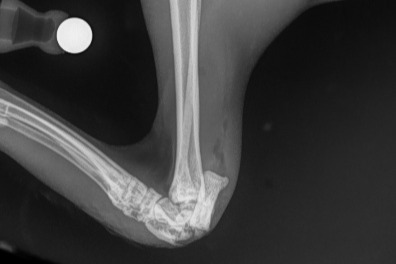

Taro is now currently in ICU on oxygen nursing broken bones in three places and has bruising to his lungs.

Both of his hind legs are badly fractured and require surgery to place pins/implants to help fuse the joints. The bones have in some parts of his leg penetrated through his skin causing an open wound.